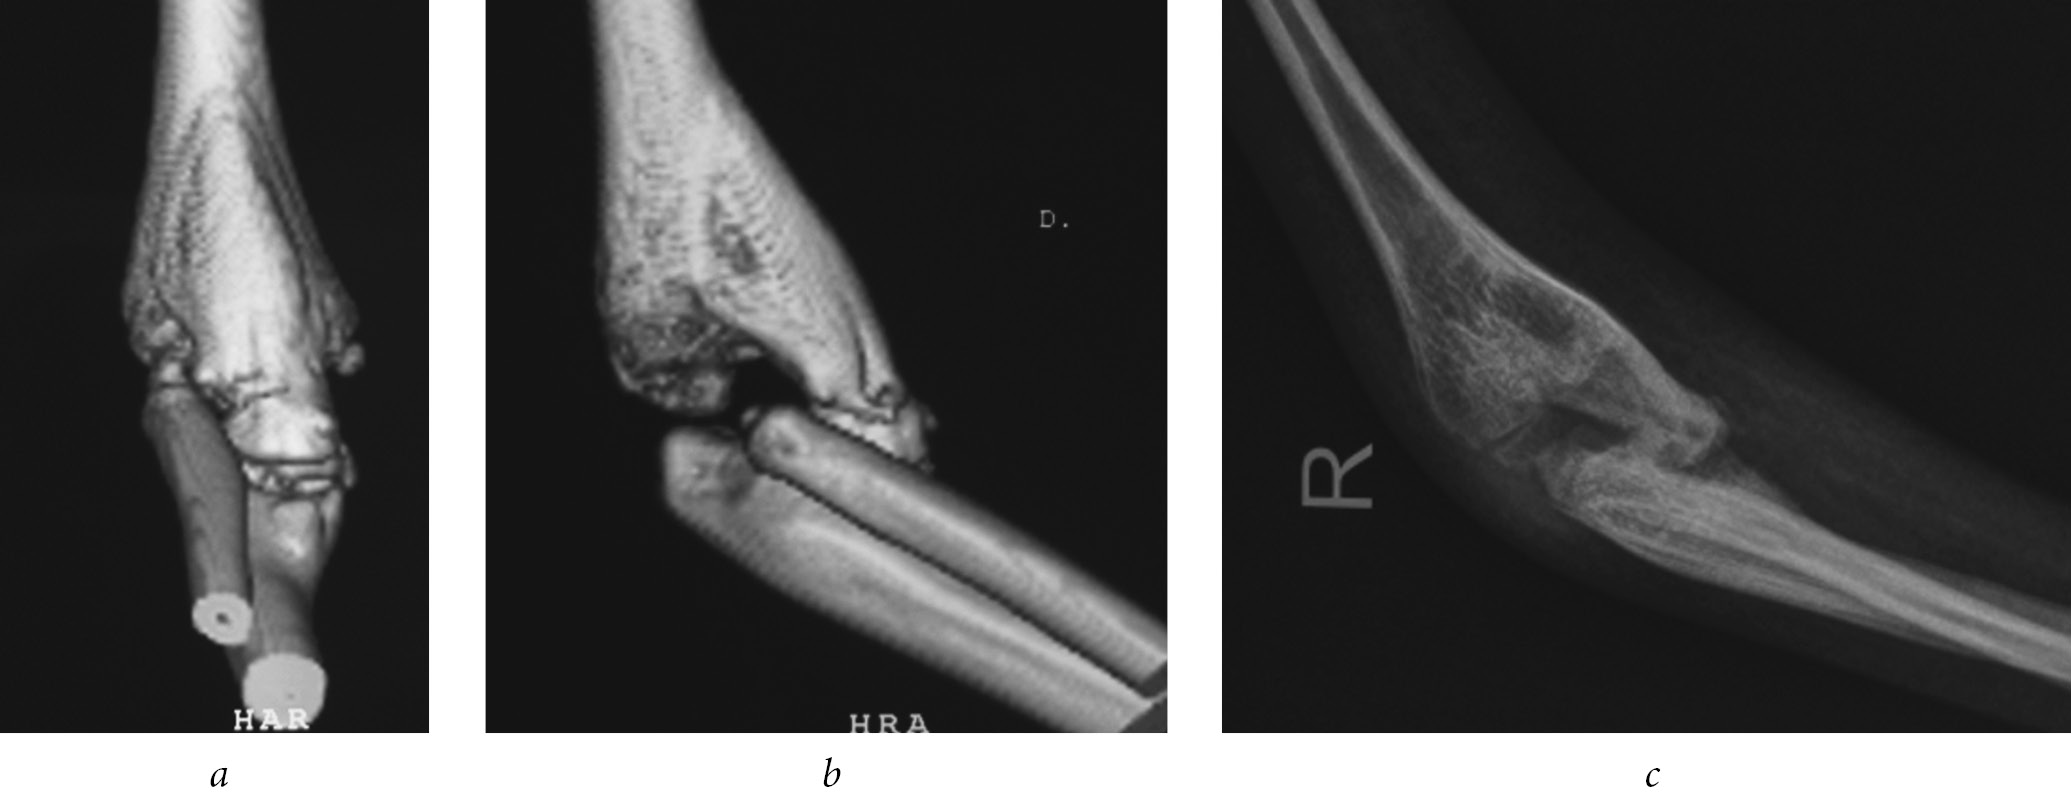

In 3.8% of patients, the elbow joint had ossified after posterior arthrolysis, which impeded flexion and extension of the elbow joint. In 2 cases, after repeated arthrolysis, the ossifications recurred, and one year after the surgery the movements became oscillating, and then ankylosis appeared at an angle of 100° (Fig. 4). Only in 1.8% of patients after repeated arthrolysis of the elbow joint and removal of ossification, was it possible to obtain the range of passive movements within 56.2 ± 3.7° at the elbow joint.

Fig. 4. Ossification of the elbow joint on the front surface of patient B., 5 years of age, after posterior arthrolysis of the elbow joint: a — computed tomography of the elbow joint, frontal view; b — computed tomography of the elbow joint, lateral view; c — a radiograohic image of an elbow joint in a lateral view